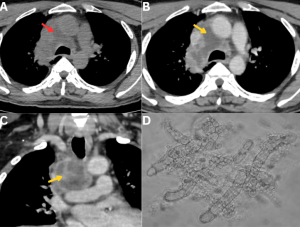

Fig 17: Clinical history:

A 35-year-old male with a history of severe COVID-19 presented to the emergency department with fever, breathlessness, and massive hemoptysis.

Figure A:

Axial CT pulmonary angiography (CTPA) image demonstrates cavitary consolidation in the right upper lobe with a pseudoaneurysm arising from the posterior segmental branch of the right pulmonary artery (red arrow).

Figure B:

Three-dimensional volume-rendered reconstruction highlights the pulmonary artery pseudoaneurysm (white arrow).

Figures C & D:

Selective pulmonary angiograms confirm a pseudoaneurysm arising from the posterior segmental branch supplying the right upper lobe (black arrows).

Figure E:

Post-glue embolization angiogram demonstrates complete occlusion of the pseudoaneurysm (green arrow).

Microbiology: Bronchoalveolar lavage culture and sputum microscopy confirmed pulmonary mucormycosis.